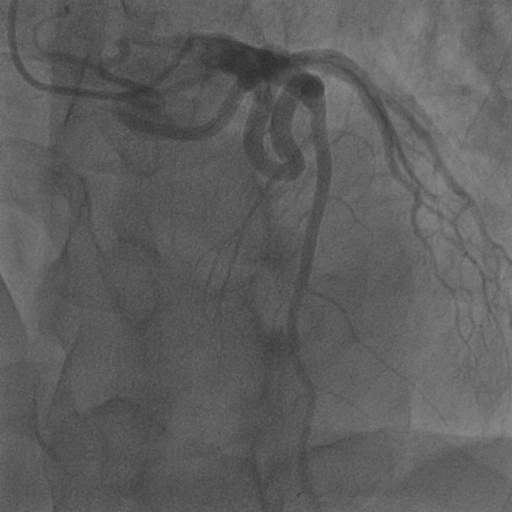

| Image | Ground truth | Video frame | Ground truth | Video frame | Ground truth |

| XCAD [33] | CADICA [19] | Our XACV dataset | |||

4.1 XACV Dataset

We collect 111 complete records of coronary artery X-ray videos, encompassing the injection, flow through the blood vessels around the heart, and dissipation of the contrast agent. Subsequently, we establish the XACV (X-ray Angiography Coronary Video) dataset. Each video consists of varying numbers of high-resolution coronary artery X-ray images. We invite experienced radiologists to annotate the vascular regions, focusing on one or two frames where the contrast agent is most prominent in each video. The XCAD dataset contains only a single image, and the CADICA video dataset does not provide corresponding ground truth. Therefore, in the following experiments, we conduct all the analyses on our collected XACV dataset and the corresponding GT for each sequence. In Figure 5, we show that compared to other publicly available datasets, XCAD [33] and CADICA [19], our dataset exhibits finer annotations in the vascular regions, providing an advantage for future related tasks. The development and use of our dataset have been approved by our institution’s IRB.